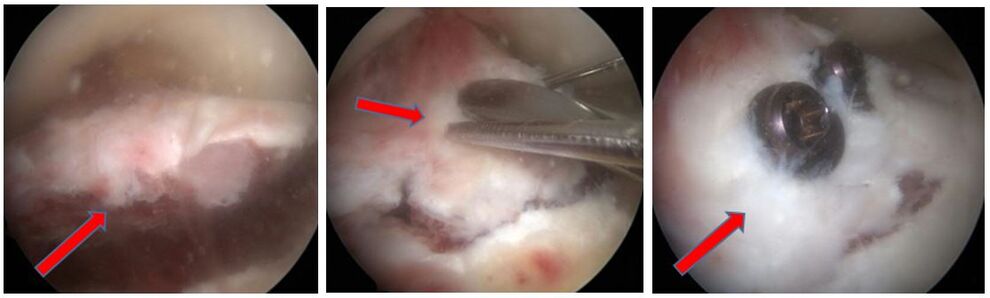

Eine Sonderform der Kreuzbandverletzung ist der knöcherne Ausriss des Bandes. Dabei kommt es bei der Verletzung nicht zu einer Ruptur des Bandes, sonders das Kreuzband reist mit einem Knochenstück ab. Meist ist dieser Ausriss dabei am Schienbeinkopf lokalisiert. Besonders gefährdet sind Kinder und Jugendliche, da bei diesen der Knochen meist weicher als die Bandstruktur ist. Die Symptome und Beschwerden entsprechen einer Kreuzbandruptur. Oft können die Verletzten das Bein nicht richtig strecken, da das Knochenstück einklemmt. Diese Verletzung ist im Gegensatz zu einer Kreuzbandruptur oft auch im normalen Röntgenbild des Kniegelenkes zu sehen. Zur Sicherung der Diagnose und um nach eventuellen Begleitverletzungen zu suchen, erfolgt oft ein MRT und manchmal auch eine Computertomographie (CT).